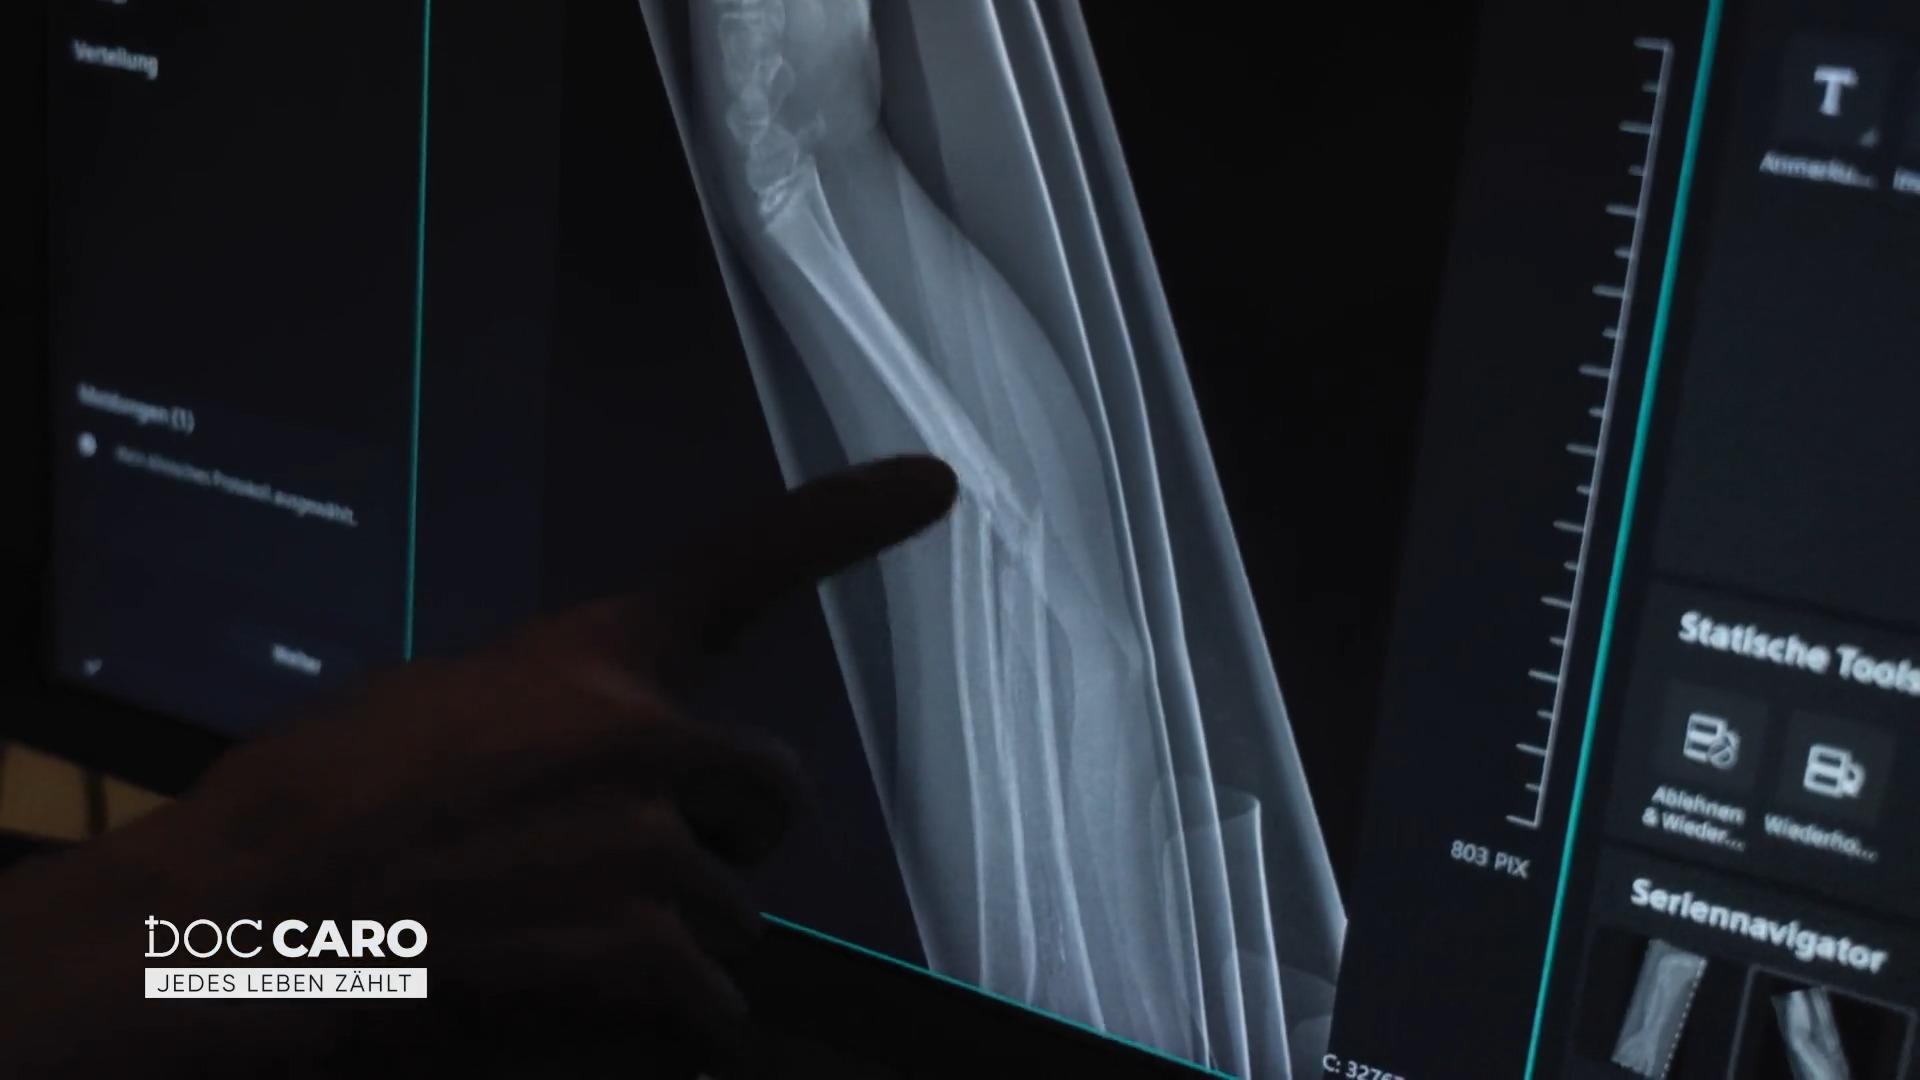

Die siebenjährige Patientin wird nicht allein gelassen. "Doc Caro" begleitet sie behutsam durch Untersuchung und Röntgen. Das Ergebnis: Der Unterarm ist gebrochen – eine Operation ist unumgänglich.